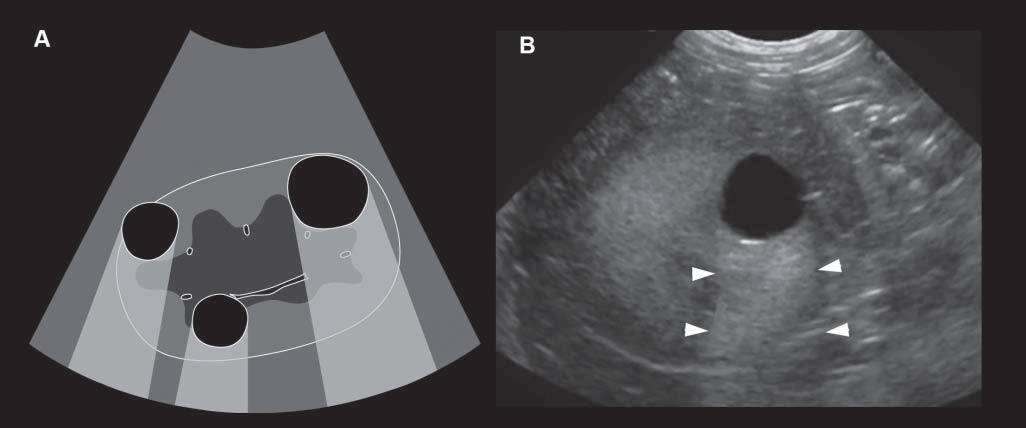

AcousticEnhancementorIncreased Through-transmission

Conversely,wavesencounteringastructurethatallows themtopassthroughmoreeasily(poorlyattenuating), suchasaliquid-filledcyst,remainofhigherintensity whenreachingthedeepertissues,allowingechoesof greaterstrengthtoreturntotheprobe.Consequently, thesedeepertissuespresentanartifactualincreasein echogenicity(Figure1.15).Acousticenhancementis typicallyrecognizeddeeptoafluid-filledstructureina softtissuebackground,suchasdeeptothegallbladder ortoalivercyst,makingthemeasytoidentifyand

Figure1.15. Enhancement.A: Thisartifactisrepresentedbyazoneofincreasedechogenicity,behindafluid-filledstructure.Onthisschematicdrawing,severalrenalcystsareseenassociatedwithdistalenhancement B: Anexampleofasimilar cystispresentinthisdog,whereitisseenasarounded,well-definedanechoicrenalcystassociatedwithfarenhancement (arrowheads).

distinguishfromsolidlesions.Tissuesdeeptothe urinarybladderandorgansfloatinginascitesoften becomehyperechoic.